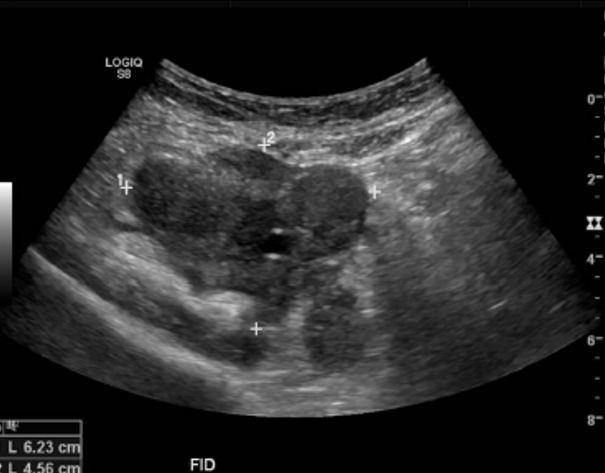

• En bazo se visualizan múltiples imágenes nodulares, sólidas, hipoecogénicas, bien delimitadas, sin señal Doppler, sugerentes de metástasis.

El bazo de tamaño normal, presenta múltiples imágenes hipoecogénicas sólidas dispersas en su parénquima, de tamaños entre 10 y 12 mm.

Múltiples nódulos en el bazo de aspecto secundario. Hidronefrosis derecha